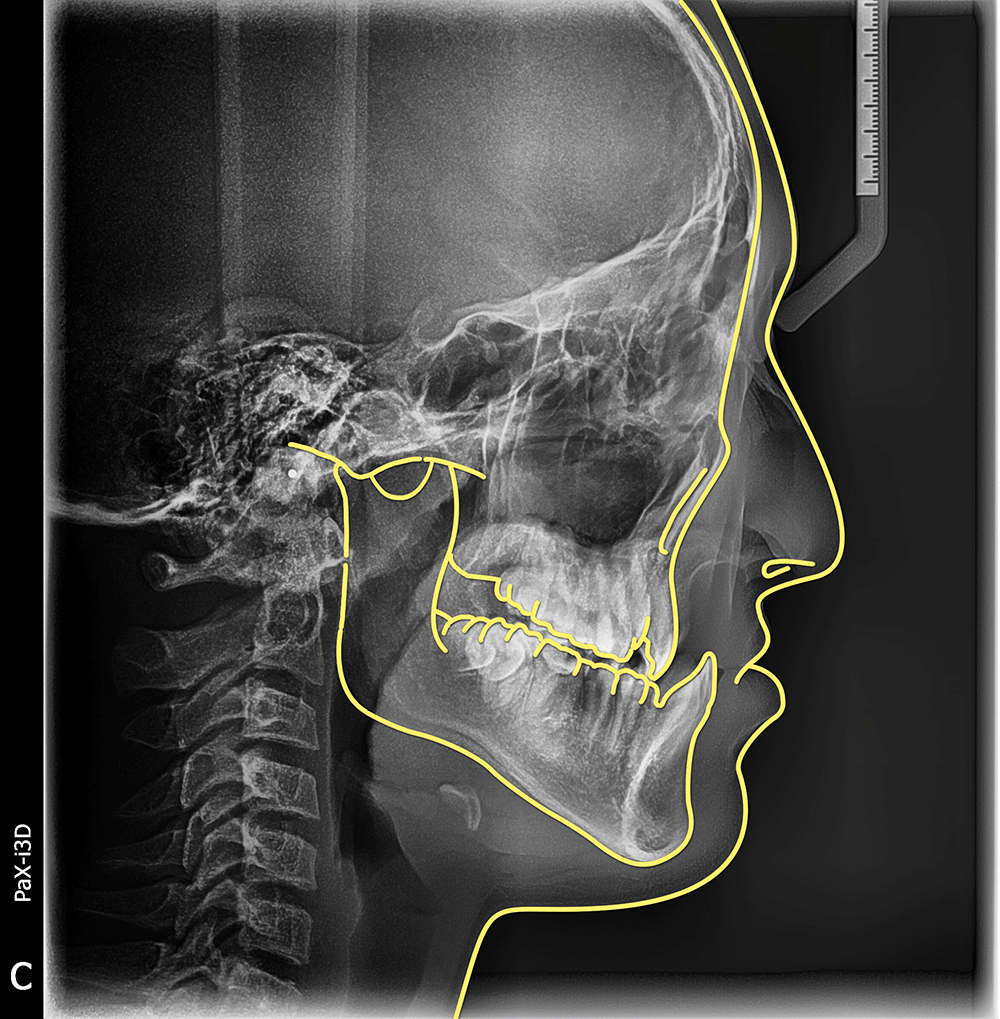

唇腭裂患者上颌骨严重发育不足

正畸治疗刺激上颌骨生长的效果

动图是严重骨性III类畸形上颌骨发育不足的患者,刺激颌骨生长前后的效果对比。

单纯正畸治疗,没有正颌哦~

以下是没画轮廓的原图